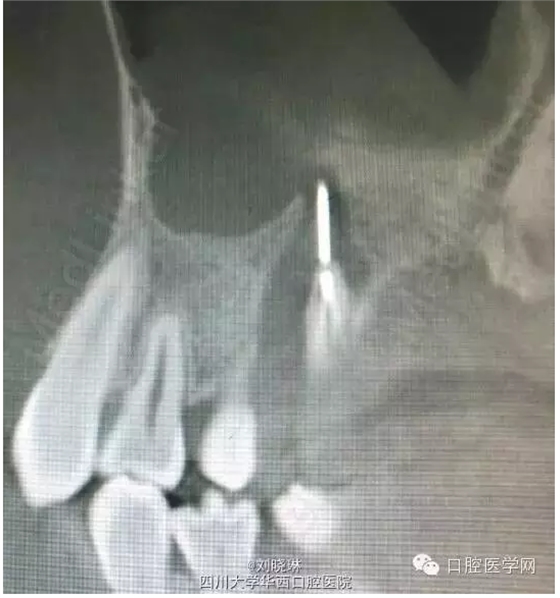

主訴:患者自訴右上后牙疼痛不適,較劇烈,自行往牙齒內(nèi)插入1縫衣針,自覺疼痛有緩解,先于我院就診。

檢查:16牙合面大面積齲損,已穿髓,可見髓腔及根管,探(-),冷(-),叩(+),無明顯松動,唇頰側(cè)未見明顯瘺道。

CBCT示:16牙合面大面積牙體組織密度減低影,與髓腔穿通,腭側(cè)根管內(nèi)可見高密度影像,超出根尖孔外至上頜竇,根尖周組織暗影。

診斷:16牙深齲穿髓

16牙慢性根尖周炎

討論:第一次看到對自己這么狠的人,患者14歲,為年輕恒牙,根管及根尖孔粗大,也導致了縫針的進入